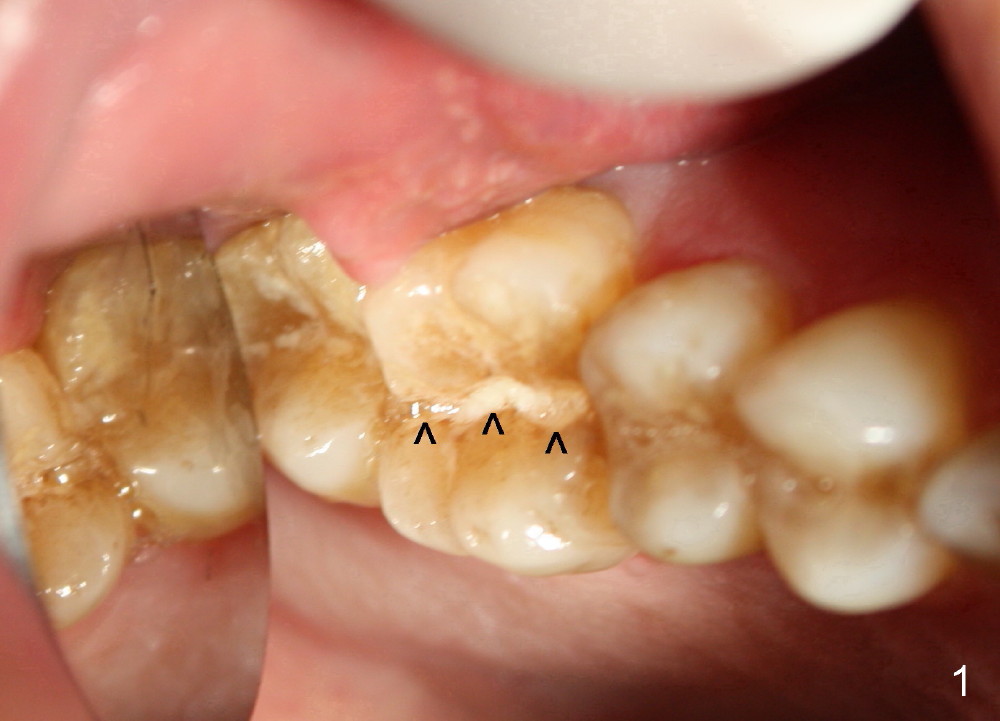

A 49-year-old man requests implant restoration of the upper 1st right molar with crack (Fig.1 ^).  He loves to chew nuts.  There is exosteotosis. In fact the upper left molar also has crown fracture.  Bone density should be high.  There is abundant bone all around.  The limiting factor will be the mesiodistal width of the septum (Fig.2 S), which is 4.87 mm.  Bone expansion may be required to place 5 mm implant.  The coronal part of the proximal surfaces of the implant may be exposed. Surgical handpiece may be needed to flatten the pointed coronal part of the septum before a 1.5 mm pilot drill is used to initiate ostetomy.  Bicon reamers are used to collect bone from the septum of #3.  Or osteotomes may be used to expand the osteotomy before implant placement.  Then place the autogenous bone with or without allograft back to the three remaining sockets and cover the thread exposed proximal surface.  The opening of the sockets will be covered by a collagen membrane, which is fixed between the crest level implant (5.0 mmx14 mm) and healing abutment (8 or 9 mm in diameter).  What happens in surgery?